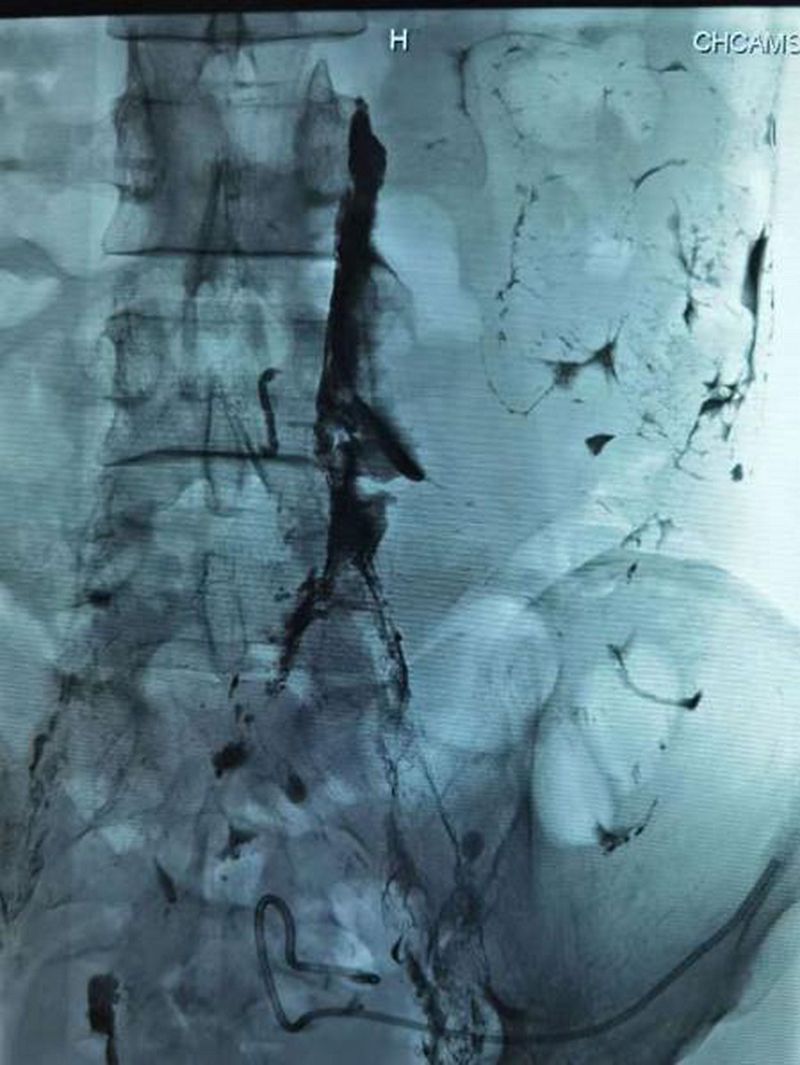

栓塞之后破口完全封堵

2021年6月9日,在介入治疗科副主任宋鹏和超声科医生的密切配合下,刘先生的左侧腹股沟淋巴结被成功穿刺,连接注射器缓慢注射造影剂,通过每间隔3-5分钟摄影,大约1小时左右淋巴管破口也被顺利地找到。在宋鹏主任的精细操作下,一根纤纤细针穿过刘先生的腹腔,精准穿刺到漏口部位,随着微导管对缺口位置再次确认及生物胶的缓缓注入,淋巴管的破口被成功封堵,手术取得了圆满成功。